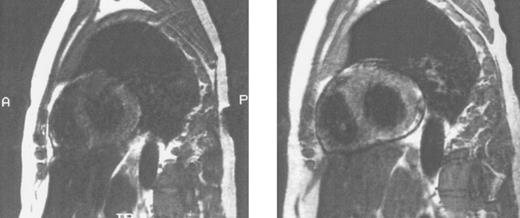

Imaging of tissue iron.Computed tomography,170-174 nuclear resonance scattering (NRS) from manganese-56,175 and the most widely used modality, magnetic resonance imaging,176-193 have all been used to evaluate tissue iron stores in vitro and in vivo, but none is clinically available for the measurement of hepatic iron concentrations. Biopsy-demonstrated reductions in hepatic iron have been reflected by magnetic resonance imaging (MRI) in individual patients192 (Fig 3), but correlations between hepatic iron concentrations determined by biopsy and those estimated by magnetic resonance have varied with differences in both equipment and method. Magnetic resonance represents the only imaging method in clinical use with the potential to detect iron within the heart189,192,193 (Fig 4). Although imprecision in the quantitation of cardiac iron obtained at biopsy194,195 prevents direct correlation with values of cardiac iron estimated by MRI in humans, good correlation between MRI-derived, and biopsy-determined, cardiac iron has been observed in a thalassemic mouse model.193 Furthermore, MRI changes consistent with the reduction of cardiac iron (Fig 5) that are paralleled by improvement in cardiac function have been reported in individual patients.192 Similarly, MRI studies of the iron-loaded anterior pituitary gland196,197 have reported variations in pituitary iron that are correlated with pituitary reserve in individual patients with thalassemia.198 In summary, although many studies show that MRI can reflect the presence of, and changes in, tissue iron in vivo, this method has not been validated as one that provides measurements of tissue iron that are quantitatively equivalent to those determined at tissue biopsy.

Sagittal MRI of cardiac iron before (left) and after (right) therapy with the orally active iron chelating agent deferiprone in the same patient with homozygous β thalassemia whose liver histology and hepatic MRI are shown in Fig 3. Imhomogenity of cardiac signal in the MRI on the left is compatible with significant iron deposition, while improvement in signal intensity after nine months of chelating therapy indicates that the cardiac iron content is reduced compared with that of the previous study. (Reprinted with permission.192 )